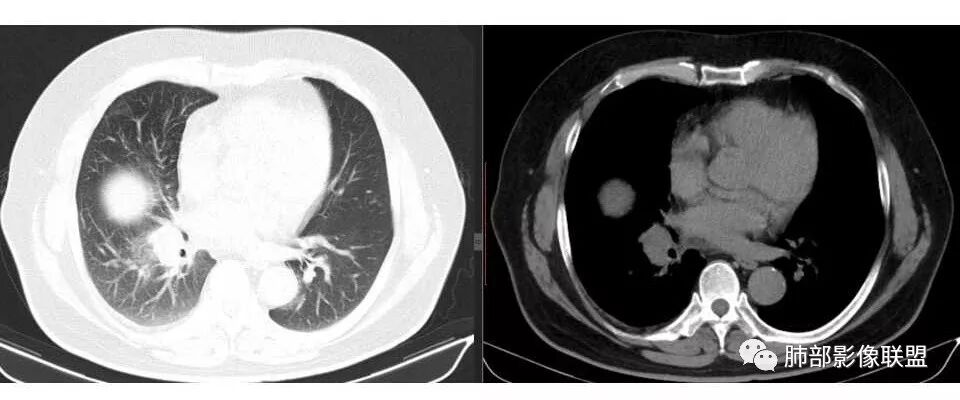

支气管狭窄,壁有侵犯

局限性中央间质增厚,考虑癌性淋巴管炎

部分区域有结节感

右侧胸膜增厚

我支持肺癌,每年体检没发现,提示进展迅速,没看到肺内大病灶,吸烟,支持小细胞癌可能

1.右肺上叶不规则结节影,右肺门及纵隔多结节并形成巨大块影,密度均匀,沿途支气管明显狭窄。

原发灶小或隐匿,肺门纵隔淋巴结异常增大,所谓“娘小崽大”常见于肺小细胞癌!

2.右肺小叶间隔增厚伴微小结节,提示癌性淋巴管炎。